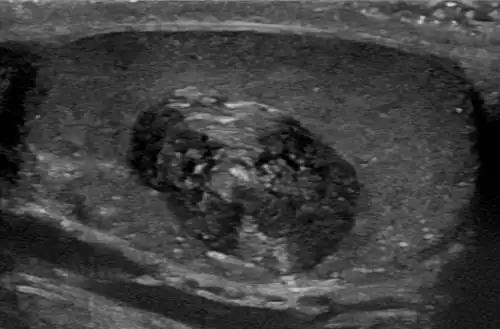

Epidermoid cyst in a testicle on ultrasound, with lamellated ("onion skin") appearance